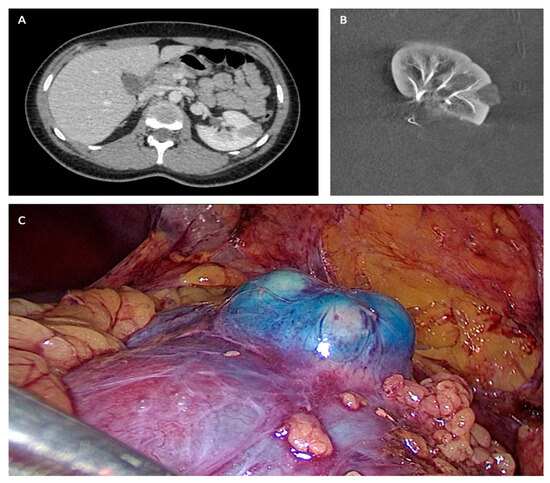

- Bigot, P.; Bouvier, A.; Panayotopoulos, P.; Aubé, C.; Azzouzi, A.R. Partial nephrectomy after selective embolization of tumor vessels in a hybrid operating room: A new approach of zero ischemia in renal surgery: Hybrid Operating Room for Kidney Surgery. J. Surg. Oncol. 2015, 113, 135–137. [Google Scholar] [CrossRef]

- Panayotopoulos, P.; Bouvier, A.; Besnier, L.; Rousselet, M.C.; Nedelcu, C.; Baize, N.; Beydon, L.; Aubé, C.; Azzouzi, A.-R.; Bigot, P. Laparoscopic partial nephrectomy following tumor embolization in a hybrid room. Feasibility and clinical outcomes. Surg. Oncol. 2017, 26, 377–381. [Google Scholar] [CrossRef]

- Bouvier, A.; Besnier, L.; Paisant, A.; Briot, T.; Hebert, T.; Daniel, V.; Beydon, L.; Marinnes, M.Z.; Baize, N.; Aubé, C.; et al. Blue Dye Embolization of Renal Tumor: A New Technique to Improve Tumor Localization During Laparoscopic Partial Nephrectomy. J. Laparoendosc. Adv. Surg. Tech. 2020, 30, 299–303. [Google Scholar] [CrossRef]